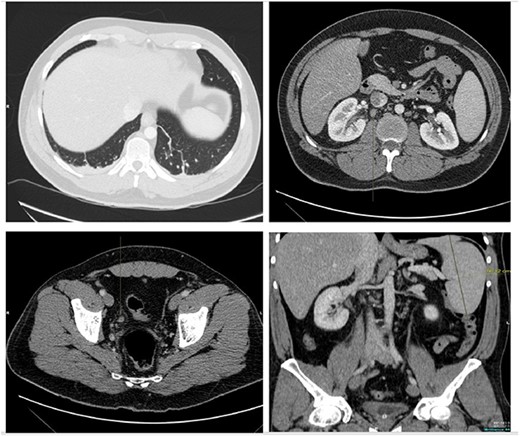

The patient was treated with IV piperacillin-tazobactam. However, he continued to have febrile temperature spikes. No growth was initially detected on blood cultures. The patient developed shortness of breath and respiratory alkalosis, for which a CT pulmonary angiography was done to exclude pulmonary embolism. Only dependent bilateral changes in the lower lobes and signs of mild pulmonary venous congestion were reported (Fig. 3). He was started on hydrocortisone, ethambutol, pyridoxine and rifampicin as empirical treatment for BCGosis. Hydrocortisone was eventually tailored down to prednisolone. Virology tests including hepatitis and immunodeficiency virus were run and these were negative. He continued spiking high temperatures and a repeat CT abdomen with IV contrast was performed which was largely unchanged from the previous scan (Fig. 4). An echocardiogram ruled out infective endocarditis. Incidentally he was in contact with a COVID-19 positive patient and was placed under quarantine for 14 days. Fortunately, he never developed COVID-19 infection. Another CT pulmonary angiography was performed in view of persisting shortness of breath but only mosaic attenuation in the lungs was present.

A CT pulmonary angiography was done to exclude pulmonary embolism. Only dependent bilateral changes in the lower lobes and signs of mild pulmonary venous congestion were noted.